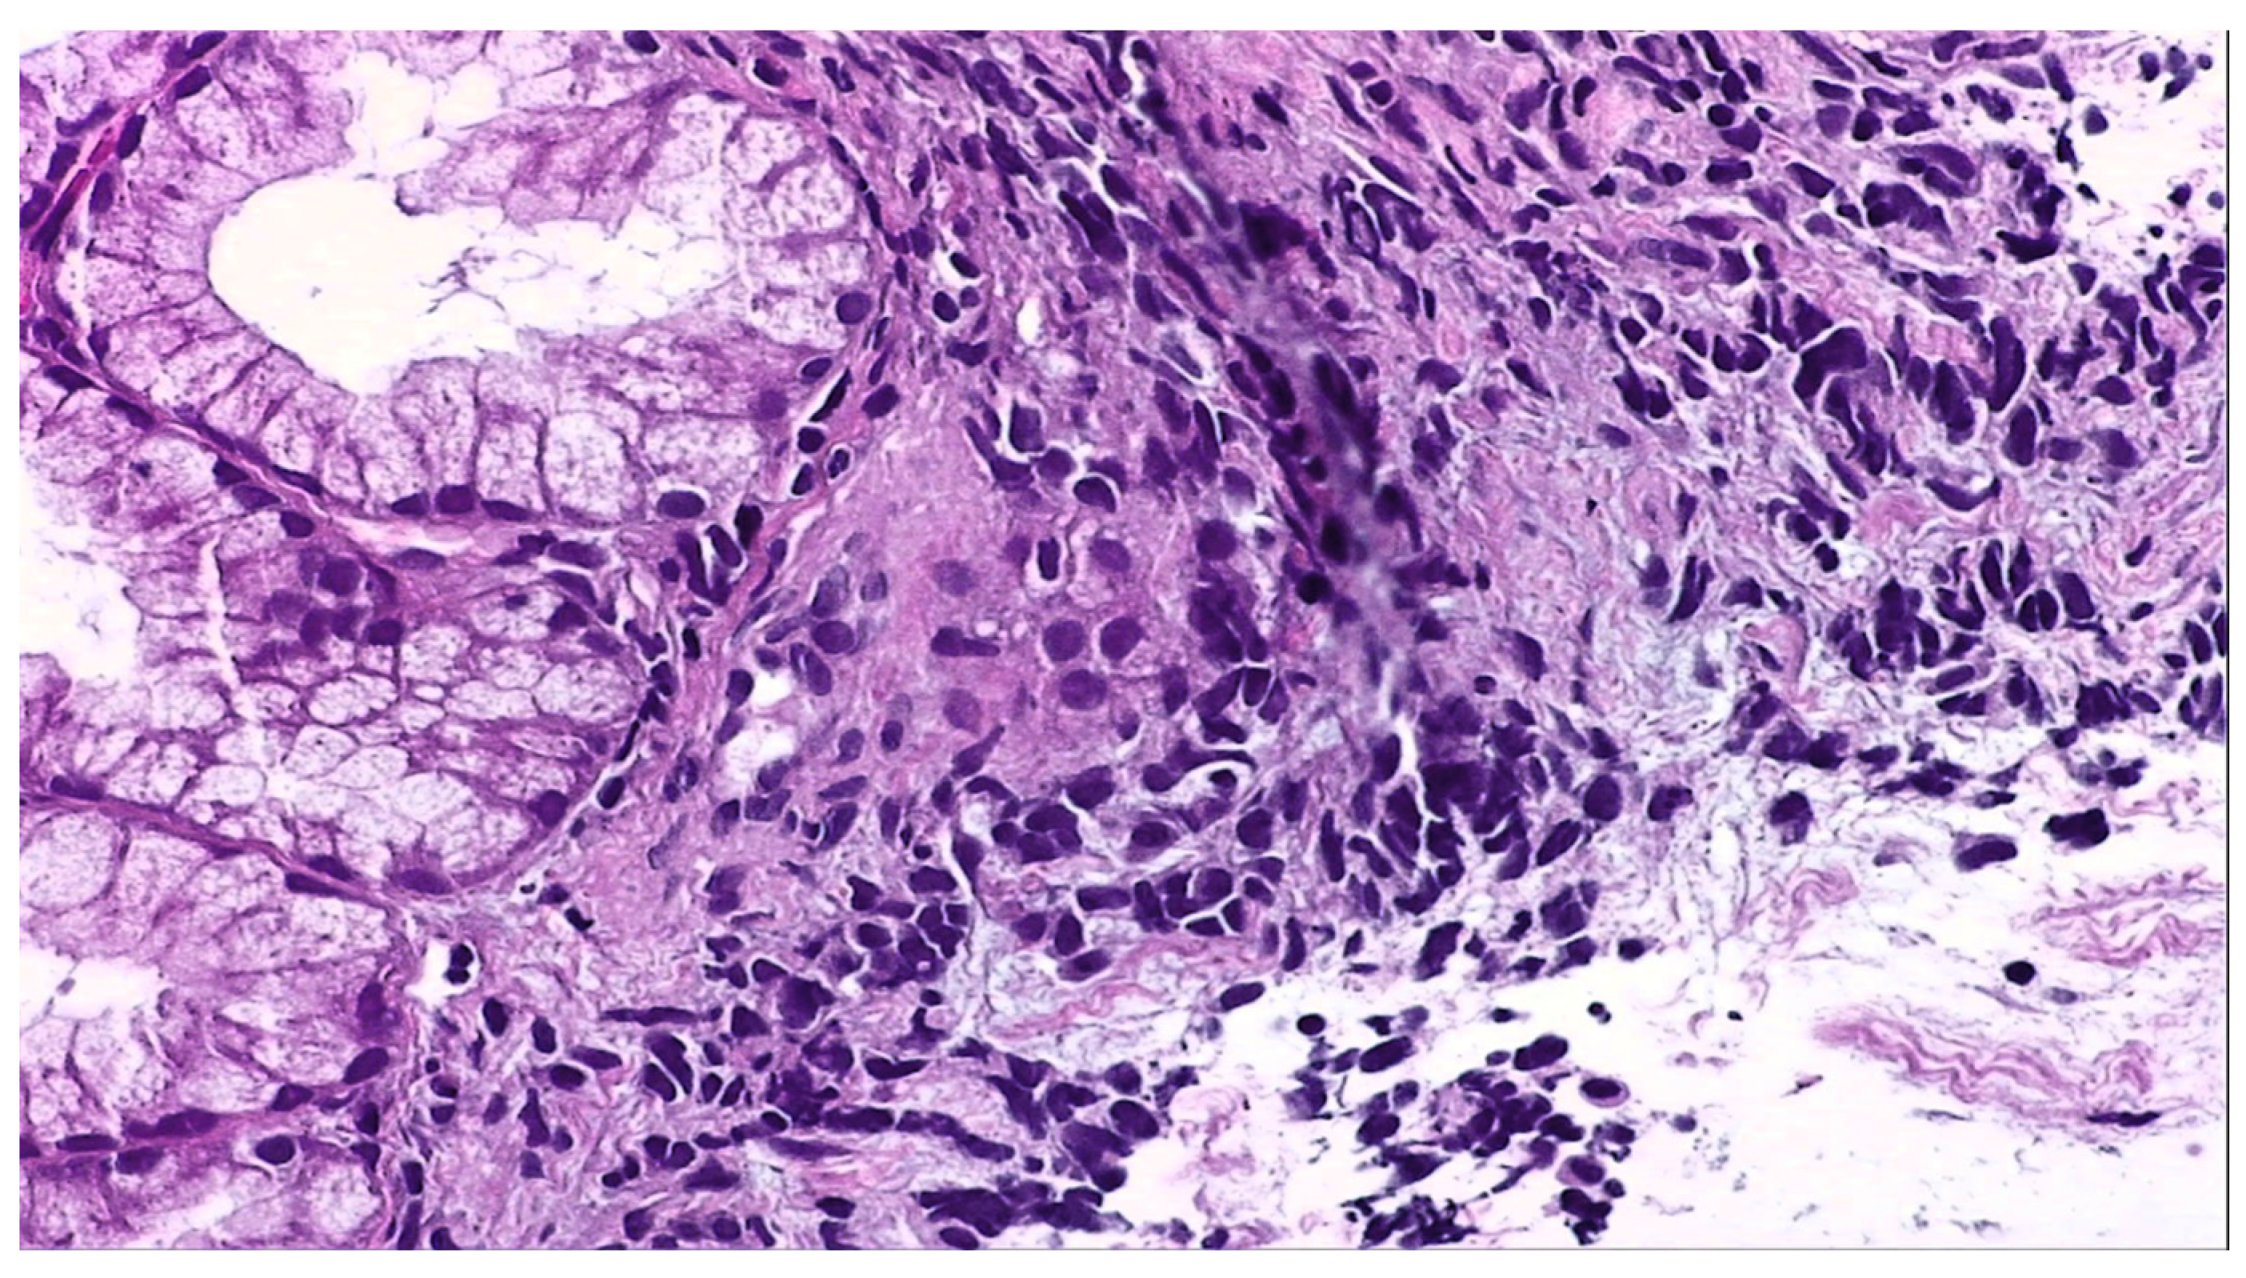

2. Detailed Case Description

2.1. Diagnostic Evaluation